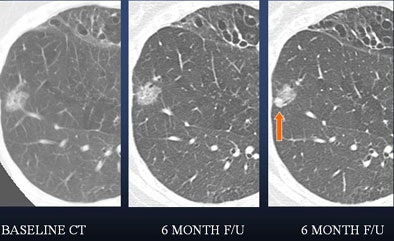

| A lung nodule detected in a 48-year-old man demonstrates highly irregular borders at six-month follow-up. PET could be helpful as a next step -- positive results would indicate more aggressive management. |